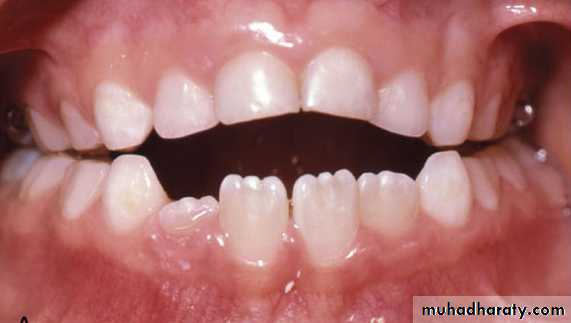

Unilateral posterior crossbite with lateral shift may result from:

• Occlusal interferences from primary canine: there is normal occlusal relations at initial contact but in centric occlusion there is mandibular shift leading to unilateral crossbite.

Initial contact

Centric occlusion

• In the majority of children with unilateral posterior crossbite there is moderate bilateral narrowing of the upper arch leading to posterior interferences upon closure. This forces the mandible to shift to a new position for maximum intercuspation.Initial contact

Marked bilateral narrowing produce no interference and the patient will have bilateral crossbite in centric relation.Less frequently unilateral posterior crossbite is caused by true unilateral narrowing of the upper arch, the patient has crossbite in centric relation and centric occlusion.

Bilateral crossbite

True unilateral crossbite